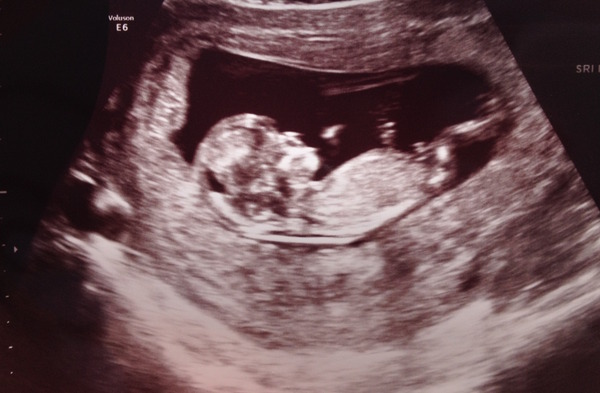

Just popping in quickly to say all ok at 12 week scan today, phew! Baby was asleep, until I made the sonographer wake it up at the end! Measuring bang on for 12 weeks and DD of 22 march confirmed. 20 week scan on 2 Nov, aggggeees away. Good luck everyone else with scans this week!

Our scan went well today - phew! I was so worked up all day with nerves that I had diarrhea (sorry!) all day - at least it solved my constipation problem lol. But everything was fine, measuring 11 wk 5, NT stuff all looked ok and due date moved to 24th March.

Isn't it just the strangest feeling seeing this tiny baby, that you weren't even 100% sure was still there, wriggle and kick and flip around ..... even though you can't feel anything yet? Still doesn't feel real, just feel in awe of it all.

Sonographer thinks its a girl and we'll have that confirmed when get harmony results in a week - eek more to worry about.

Also loving seeing all these cute scan pics!!! Keep them coming! Smile